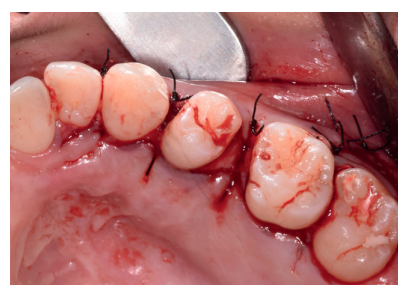

Los fragmentos coronal y radicular procedentes del tercer molar inferior y del premolar superior se limpiaron de restos de tejidos blandos y, secos, se introdujeron en la máquina Smart Dentin Grinder® (Kometa Bio, BIONER, España), tal y como aparece en la Figura 14. Tras un ciclo de triturado de 3 segundos, y otro de tamizado de 20 segundos, el material obtenido se limpió con la primera solución durante 12 minutos, y después durante 3 minutos con la segunda solución (Figura 15), para después transportar el material de injerto al alveolo, con presión controlada (Figura 16). Una vez compactado, se colocó una membrana de colágeno (Figura 17) y se suturó la herida con seda de 4/0, mediante puntos periodontales en las papilas (Figura 18). Se realizó una radiografía panorámica en el postoperatorio inmediato (Figura 19).